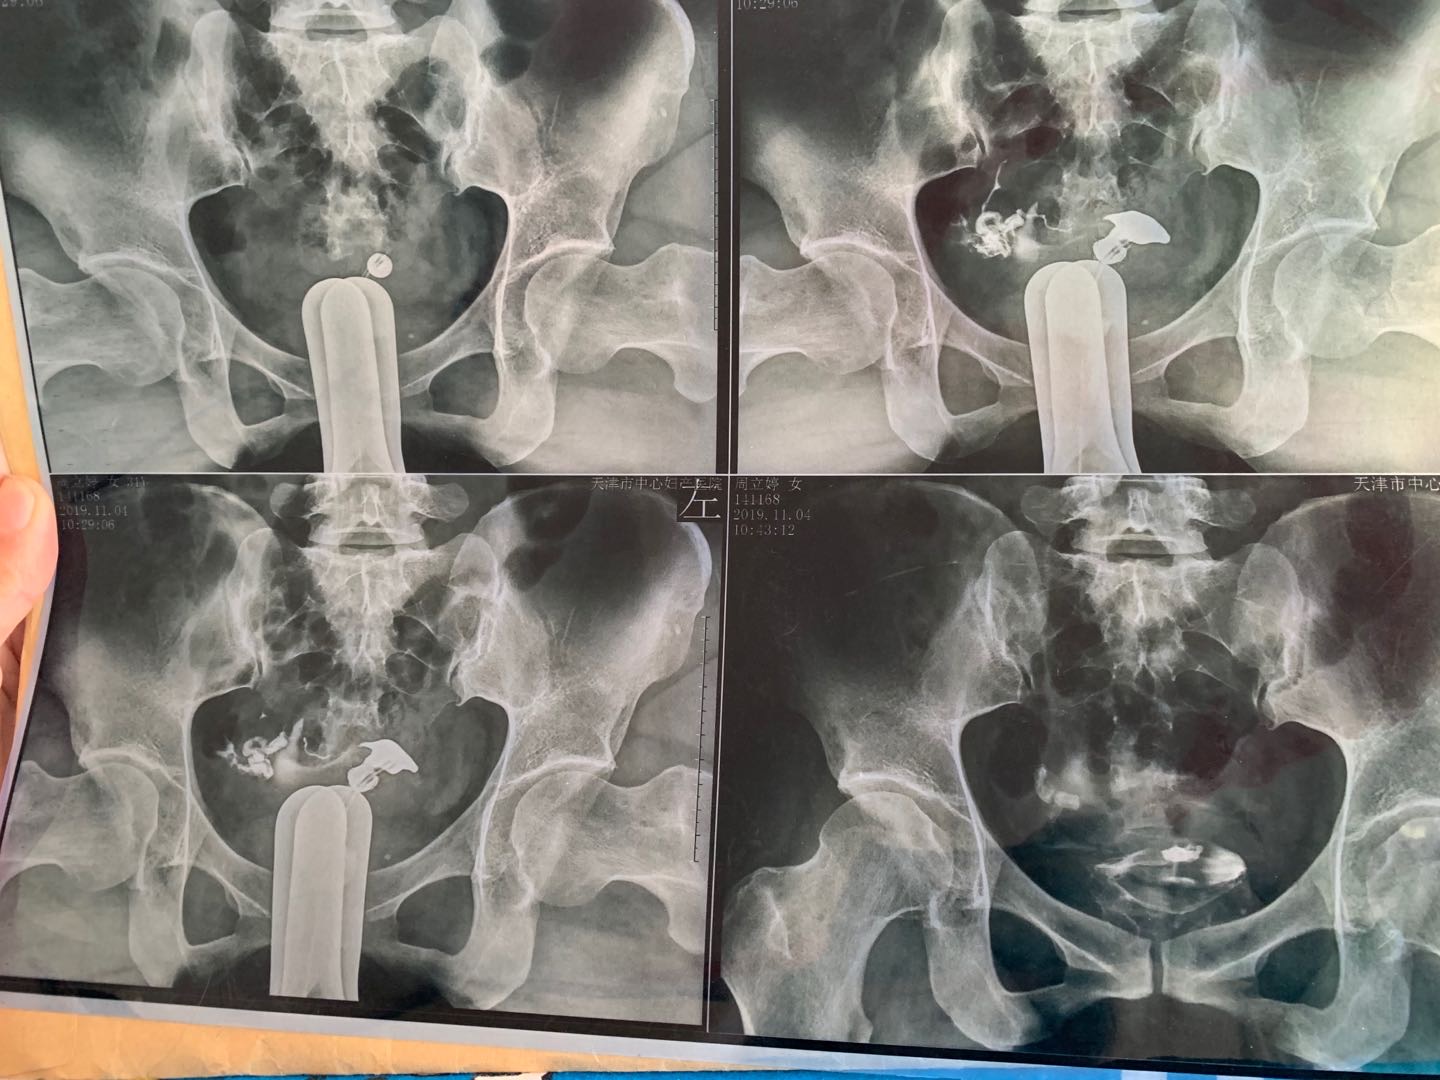

我今年34岁,右侧输卵管粘连,左侧宫外孕输卵

做完输卵管造影第六天了小腹还是感觉沉甸甸的如